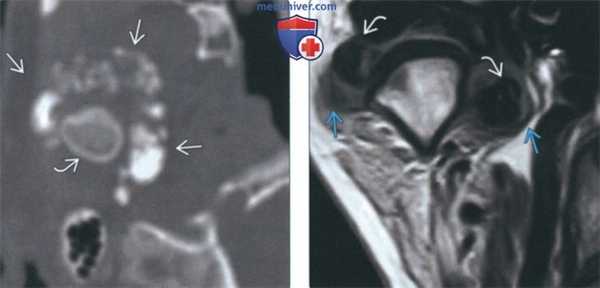

(Слева) На панорамной реформатированной КЛКТ правый мыщелок выглядит увеличенным за счет остеохондромы. Ипсилатеральные отделы тела и ветвь нижней челюсти не увеличены, что помогает отличить остеохондрому от гиперплазии мыщелка.

(Справа) На сагиттальной реформатированной КЛКТ у этого же пациента визуализируется остеохондрома, придающая мыщелку форму, слегка напоминающую луковицу. Суставная ямка не изменена. (Слева) На корональнойреформатированной КЛКТ у этого же пациента на верхней поверхности мыщелка визуализируется остеохондрома В. Трабекулярная и кортикальная кость мыщелка продолжается в опухоль. Видны неизмененные внутренние и наружные отделы мыщелка.

(Справа) На панорамной реформатированной КЛКТ визуализируется остеохондрома В отходящая от верхней поверхности правого мыщелка. Верхний край опухоли вогнут (реакция приспособления к суставному возвышению). (Слева) На панорамной реформатированной КЛКТ визуализируется остеохондрома, отходящая от передней поверхности левого мыщелка. Трабекулярная кость в опухоли переходит в трабекулярную кость мыщелка и неотличима от нее. Обратите внимание на низкое положение мыщелка в суставной ямке.

(Справа) На аксиальной КЛКТ у этого же пациента визуализируется большая остеохондрома отходящая от передней поверхности левого мыщелка. Кортикальная и трабекулярная кость опухоли выглядят аналогично мыщелку.